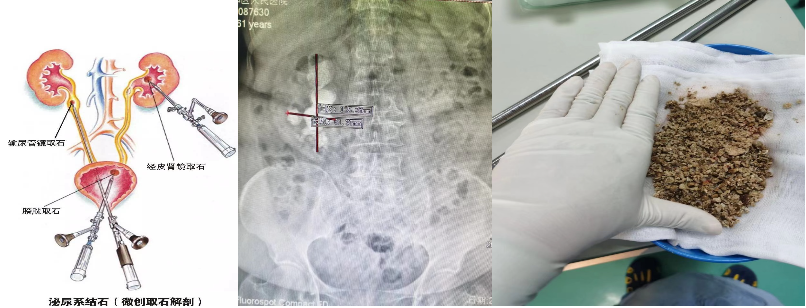

(一) 泌尿系结石微创手术治疗:经皮肾镜技术、输尿管镜、输尿管软镜等微创手术。

泌尿系结石微创手术治疗利用人体自然通道或在腰部取一铅笔粗细小孔进行手术,对患者身体达到微创甚至无创效果。本学科的微创外科手术技术已进入省市先进行列,在上尿路结石治疗的微创技术领域有丰富的手术经验,可以治疗鹿角状结石、多发性肾结石、小儿泌尿系结石、孤立肾结石和开放手术后的残留结石、复发结石、等多种复杂病例,并取得了良好的临床治疗效果,目前已经完成泌尿系结石的微创手术上万台。是广州北部地区完成此项手术例数最多的单位。